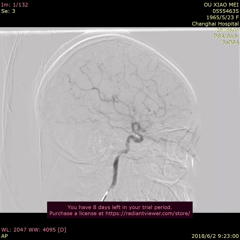

NUMEN Case 4